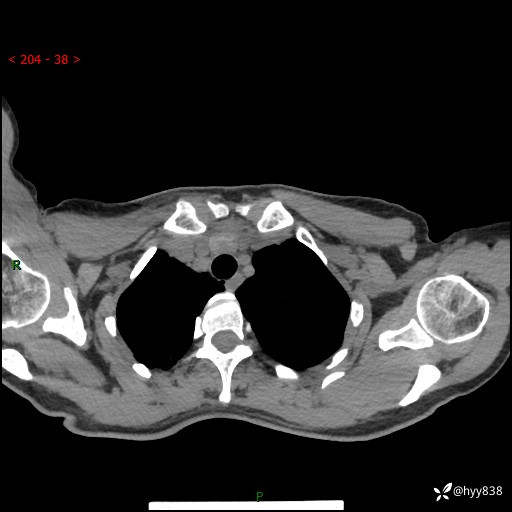

胸部CT平扫